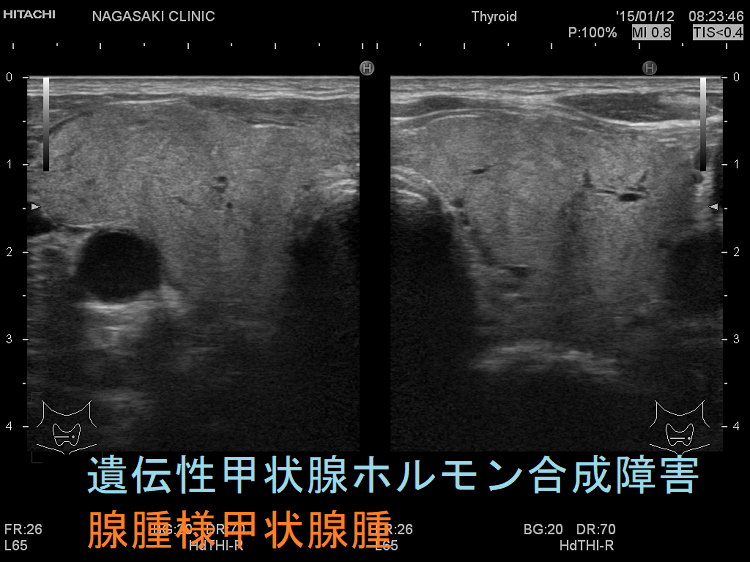

ケース①

ケース②

遺伝性甲状腺ホルモン合成障害で、サイログロブリン異常症(サイログロブリン遺伝子異常症)以外は、血中サイログロブリンが上昇するにも関わらず、甲状腺自体の破壊性変化に乏しく、マシュマロ様の軟らかい腺腫様甲状腺腫の形態を取る事があります。

遺伝性甲状腺ホルモン合成障害の超音波(エコー)画像は色々なパターンがあります。

- 常染色体優性遺伝型;腺腫様甲状腺腫の形態になります。